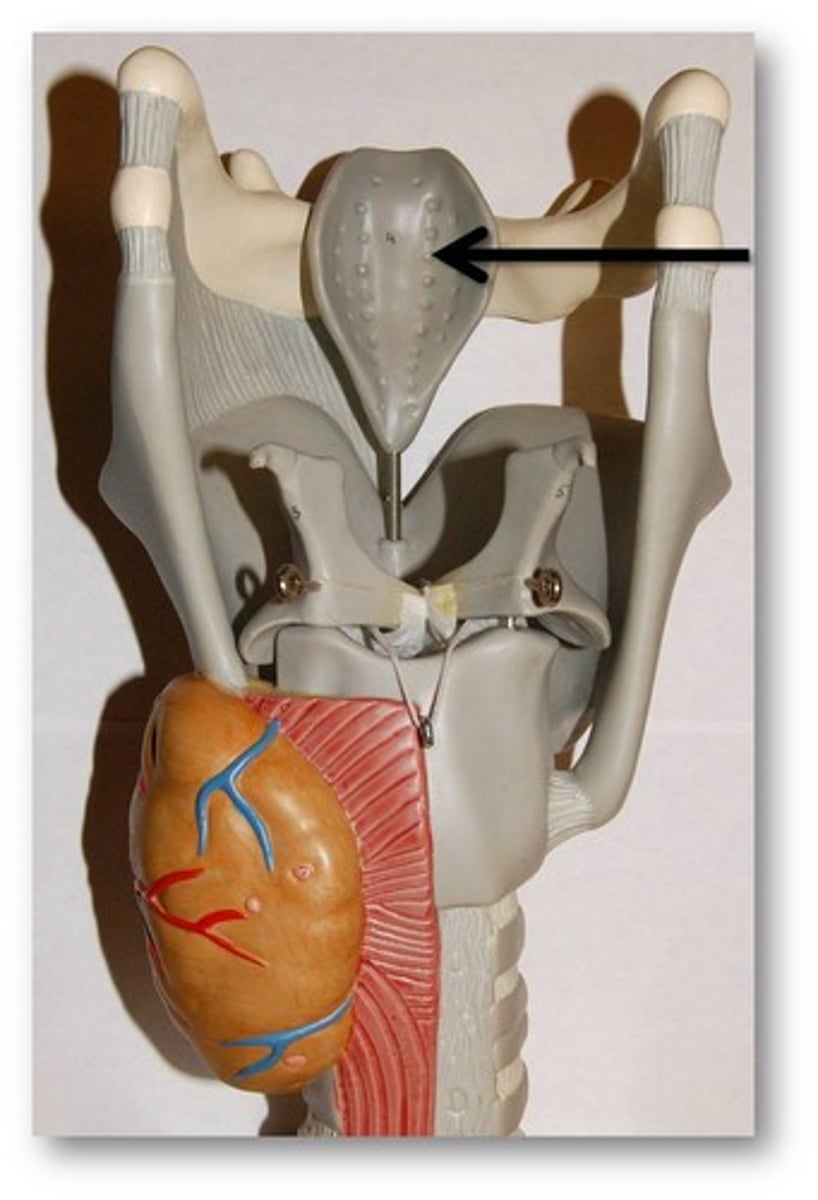

Hyoid Bone

U-shaped bone at the base of the tongue that supports the tongue and its muscles

Larynx

Voice box; passageway for air moving from pharynx to trachea; contains vocal cords

Laryngeal Cartilages

Largely construct the larynx (voice box)

Thyroid Cartilage

A firm prominence of cartilage that forms the upper part of the larynx; the Adam's apple

Cricoid Cartilage

The ring-shaped structure that forms the lower portion of the larynx

Epiglottis

A flap of cartilage at the root of the tongue, which is depressed during swallowing to cover the opening of the windpipe